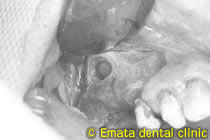

サイナスリフト治療中

開窓(骨の削除)はお痛みや腫れが出ないように出来るだけ小さくします。

サイナスリフト(ラテラルウインドウテクニックによる上顎洞底挙上術)にて同時インプラント埋入しました。